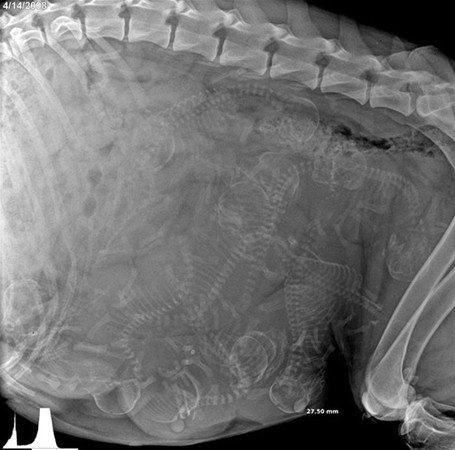

Hamile ber köpeğin röntgen filmi

<p>Hamile ber köpeğin röntgen filmi</p>